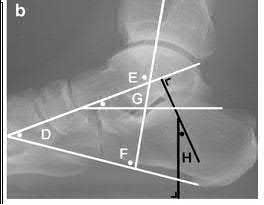

Illustration A demonstrates fibular malreduction with dislocation of the fibula anterior to the tibial incisura. Illustration B shows a comminuted fibula fracture along with a measurement of length from an intact fibula. The arc from the lateral process of the talus to the peroneal groove of the distal fibula is known as the "dime" sign and should remain unbroken if fibular length has been restored. Illustration C demonstrates the use of a push-pull screw and lamina spreader to regain length intraoperatively for a comminuted fibula fracture.

Chu and Weiner review management of malunions of the distal fibula. The authors state that restoration of fibular length, alignment and rotation leads to reduction of the talus, provides a buttress to talar motion in the setting of an incompetent deltoid, and allows the syndesmotic ligaments to heal at the appropriate tension.